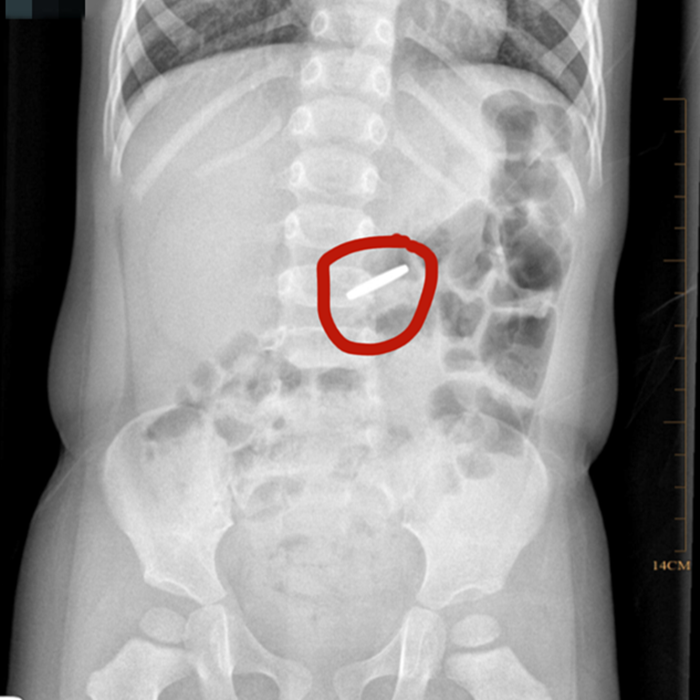

溫附二兒科消化專家胡偉國(guó)主任醫(yī)師會(huì)診后,立即為小京京開(kāi)具X光片檢查,發(fā)現(xiàn)異物滯留于胃部,考慮到硬幣長(zhǎng)時(shí)間在胃內(nèi)可能引起胃黏膜損傷,胡偉國(guó)馬上聯(lián)系麻醉科、內(nèi)鏡中心,在靜脈麻醉下為小京京行內(nèi)鏡下胃內(nèi)異物取出術(shù)。

術(shù)中發(fā)現(xiàn)硬幣果然還在胃里,好在胃黏膜無(wú)受損,胡偉國(guó)主任通過(guò)專用異物鉗很快將硬幣取出。該硬幣直徑約19毫米,已被胃液略微腐蝕。